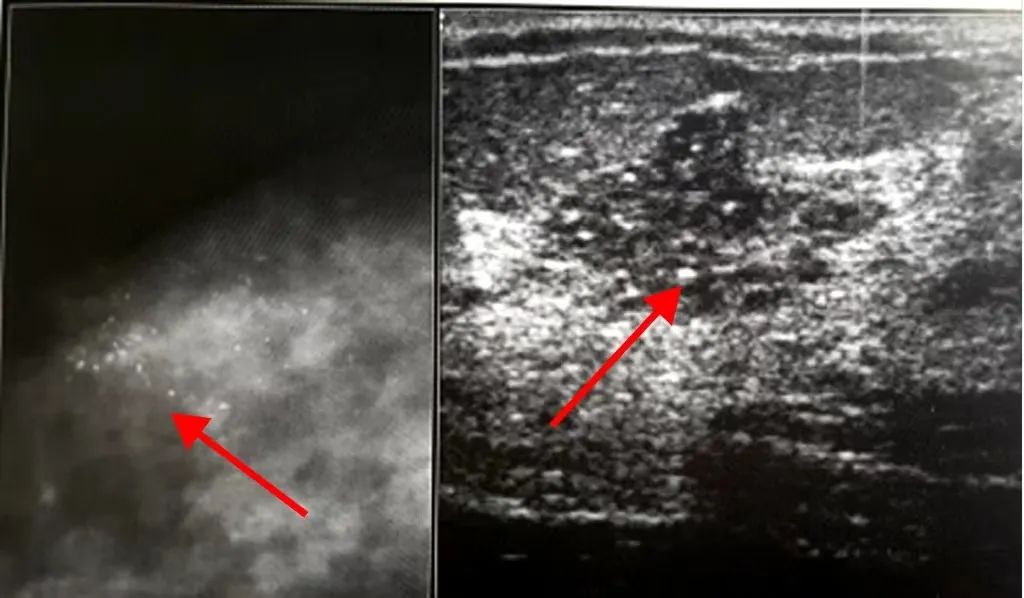

所谓钙化,是指乳腺病变影响代谢而在乳腺内产生的钙质沉积物,钙化在超声图像上表现为白色的亮点。

良性钙化多数是由于组织发生坏死、机化后钙盐沉积所致。通常表现为散发的、粗大的钙化灶,这类钙化一般无需过多担忧。

恶性钙化多数由于肿瘤分泌所致。这类钙化一般表现为成簇状、泥沙样;每平方厘米>10个的钙化;沿乳管分布很密集。出现这类钙化就需要我们的密切关注。